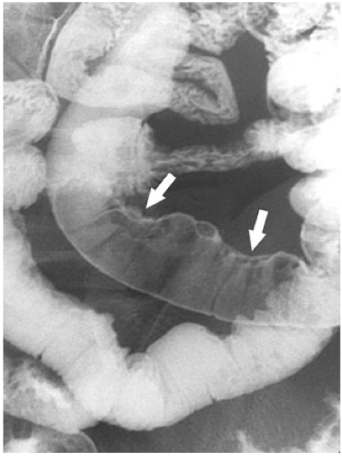

What is this

Ulcerative colitis